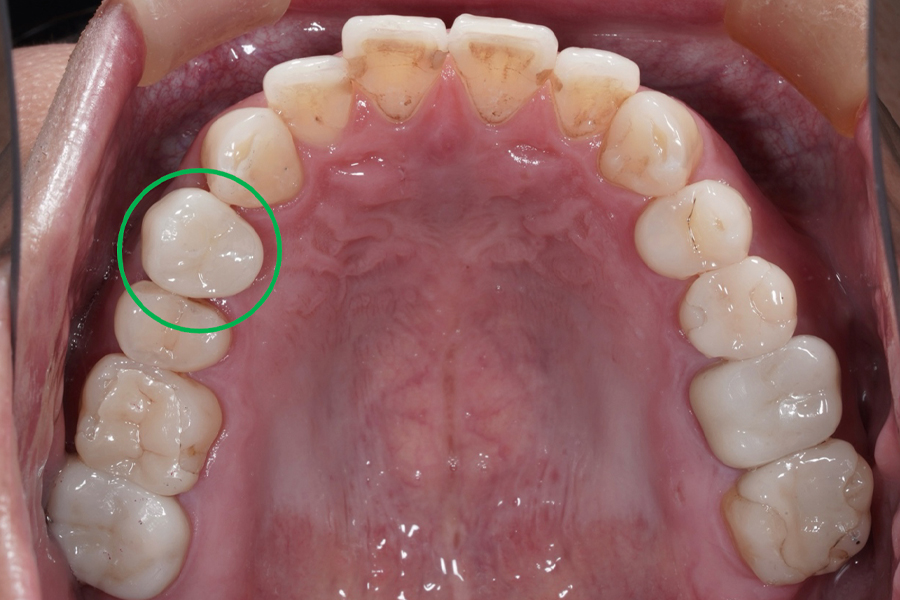

治療前(Before)

⚫︎歯質の残存量が少なく、保存困難

⚫︎周囲歯は健全

⚫︎ブリッジによる切削は回避したいご希望

⚫︎部位:右上第一小臼歯(4番)

| 主訴 | 咬合時の違和感と匂いがする。 |